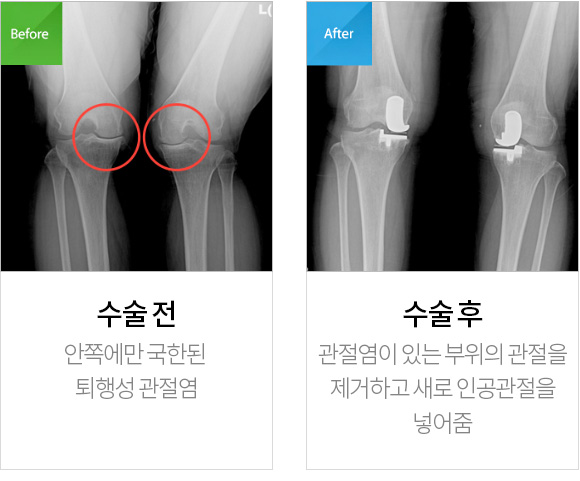

바른세상병원의 믿을 수 있는

인공관절 부분치환술

Before & After